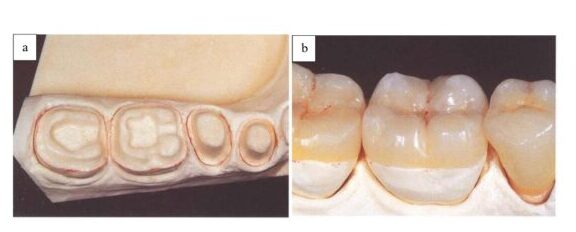

Vào những năm trước đây, các vật liệu và kĩ thuật phục hồi thẩm mỹ cho nhóm răng cối hầu như không thể cạnh tranh nổi với vật liệu amalgam hoặc vàng (H2-2, H2-3) vì những thiếu sót về mặt sinh học và lý hóa của chúng (H2-4).

Các kỹ thuật phục hồi thẩm mỹ cho răng sau có thể được phân loại thành ba nhóm (H4-1): các kỹ thuật “trực tiếp” chỉ bao gồm các thủ thuật trong miệng và thực hiện trong một lần hẹn duy nhất, kỹ thuật “bán trực tiếp” bao gồm các bước trong miệng hoặc ngoài miệng để tạo ra các phục hồi tại ghế, sau đó gắn trong cùng lần hẹn, và kỹ thuật “gián tiếp”, yêu cầu một vài lần hẹn và sự hợp tác của labo để chế tác phục hồi.

Các bác sĩ lâm sàng đều đồng ý rằng, kĩ thuật phục hồi trực tiếp chỉ nên thực hiện cho những lỗ sâu có kích thước từ nhỏ đến trung bình (H4-4 a-d)

Những xoang I, xoang II có kích thước lớn cũng như những phục hồi bán phần thì thường ưu tiên chỉ định phục hồi dán, lý tưởng nhất là có thể khôi phục một răng đơn lẻ hoặc một số răng giới hạn (hai đến ba răng phân bố trong các phần hàm khác nhau) bằng cách sử dụng kỹ thuật bán trực tiếp.

Nếu phải điều trị nhiều răng trên dưới cùng một lúc thì thường khó tạo được hình thể mặt nhai đúng giải phẫu và khớp cắn chức năng do các quy trình cơ bản của kỹ thuật bán trực tiếp như điêu khắc mặt nhai mà không có răng đối kháng phù hợp. Do đó, các kỹ thuật gián tiếp nên được chỉ định cho phục hồi toàn bộ cung răng hoặc từng phần hàm (H4-4 i-l).

Các phục hồi dán được thực hiện tại labo sẽ giúp kiểm soát khớp cắn và đạt thẩm mỹ tốt hơn. Đối với những phục hồi mở rộng (onlay hoặc overlay) thì thực hiện bằng kỹ thuật gián tiếp cũng được khuyến cáo.